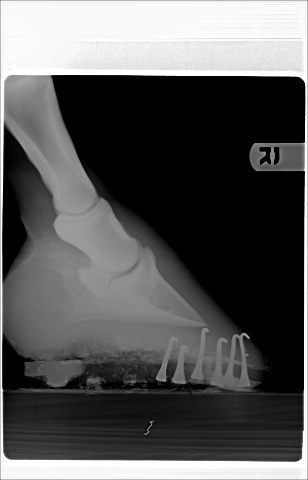

Posted on Tuesday, Apr 26, 2005 - 11:25 pm: This vet seems to feel that the farrier's work is to blame...however, he also respects my farrier and thinks I made a good choice.Here are the xrays from the farrier series.

Posted on Wednesday, Apr 27, 2005 - 7:24 pm: I was just thinking his toes looked long and I was impressed by the number of nails plus clips to hold the shoes on. If his angles are different than they normally are, or if they were changed very much in one shoeing, it could be enough to make the horse lame, at least for a while. I don't feel qualified to comment on anything else, but think you should wait for Dr. O's comments. |

Posted on Thursday, Apr 28, 2005 - 8:22 am: Concerning your vets statements no I do not think the injections were diagnostic one way or the other and agree with Sara, if at all possible I would like to see the toe squared off more.DrO |

Posted on Wednesday, Jul 20, 2005 - 12:49 am: Dear Aileen,In viewing your xrays, I am wondering if the nail closest to the apex of the (I don't know the exact name) bone, in the right front is supposed to be that close to that bone. Do you know Dr.O ? The hind looks too short. The front right has a longer toe and higher heel. The left has a lower heal and a more rounded toe. It may be the photo but they look uneven to me. I have been through 3 shoers in six years. All with impeccable resumes. Go figure. There is a Farrier College/Hoof Hospital in Salinas, California. I have heard people trailer in from different states all the time just to get a horse shod correctly once. Then a good farrier can follow the balance of all 4 hooves. Brave is gorgeous. I do agree with the others, he could lose a little in the middle. Especially during this tremendous summer heat wave. All of the top trainers keep their horses quite fit. Although photos do add weight to any image.  Good Luck!! WTG |

Posted on Wednesday, Jul 20, 2005 - 7:36 am: WTG since the radiographs are 2 dimensional and we only have lateral views you cannot evaluate the nails positions with respect to the bone. For instance the nail could be tapped to the outside of the foot and would have the same appearance.Ailleen the angles, distance, and low light make evaluation difficult. Better would be to maintain the distance but to telephoto in just a bit to the point where you get distal cannon, fetlock and hook. Flash or outside with the sun behind you will improve the lighting. Also the closer the camera is to the ground, to avoid foreshortening, the better. DrO |